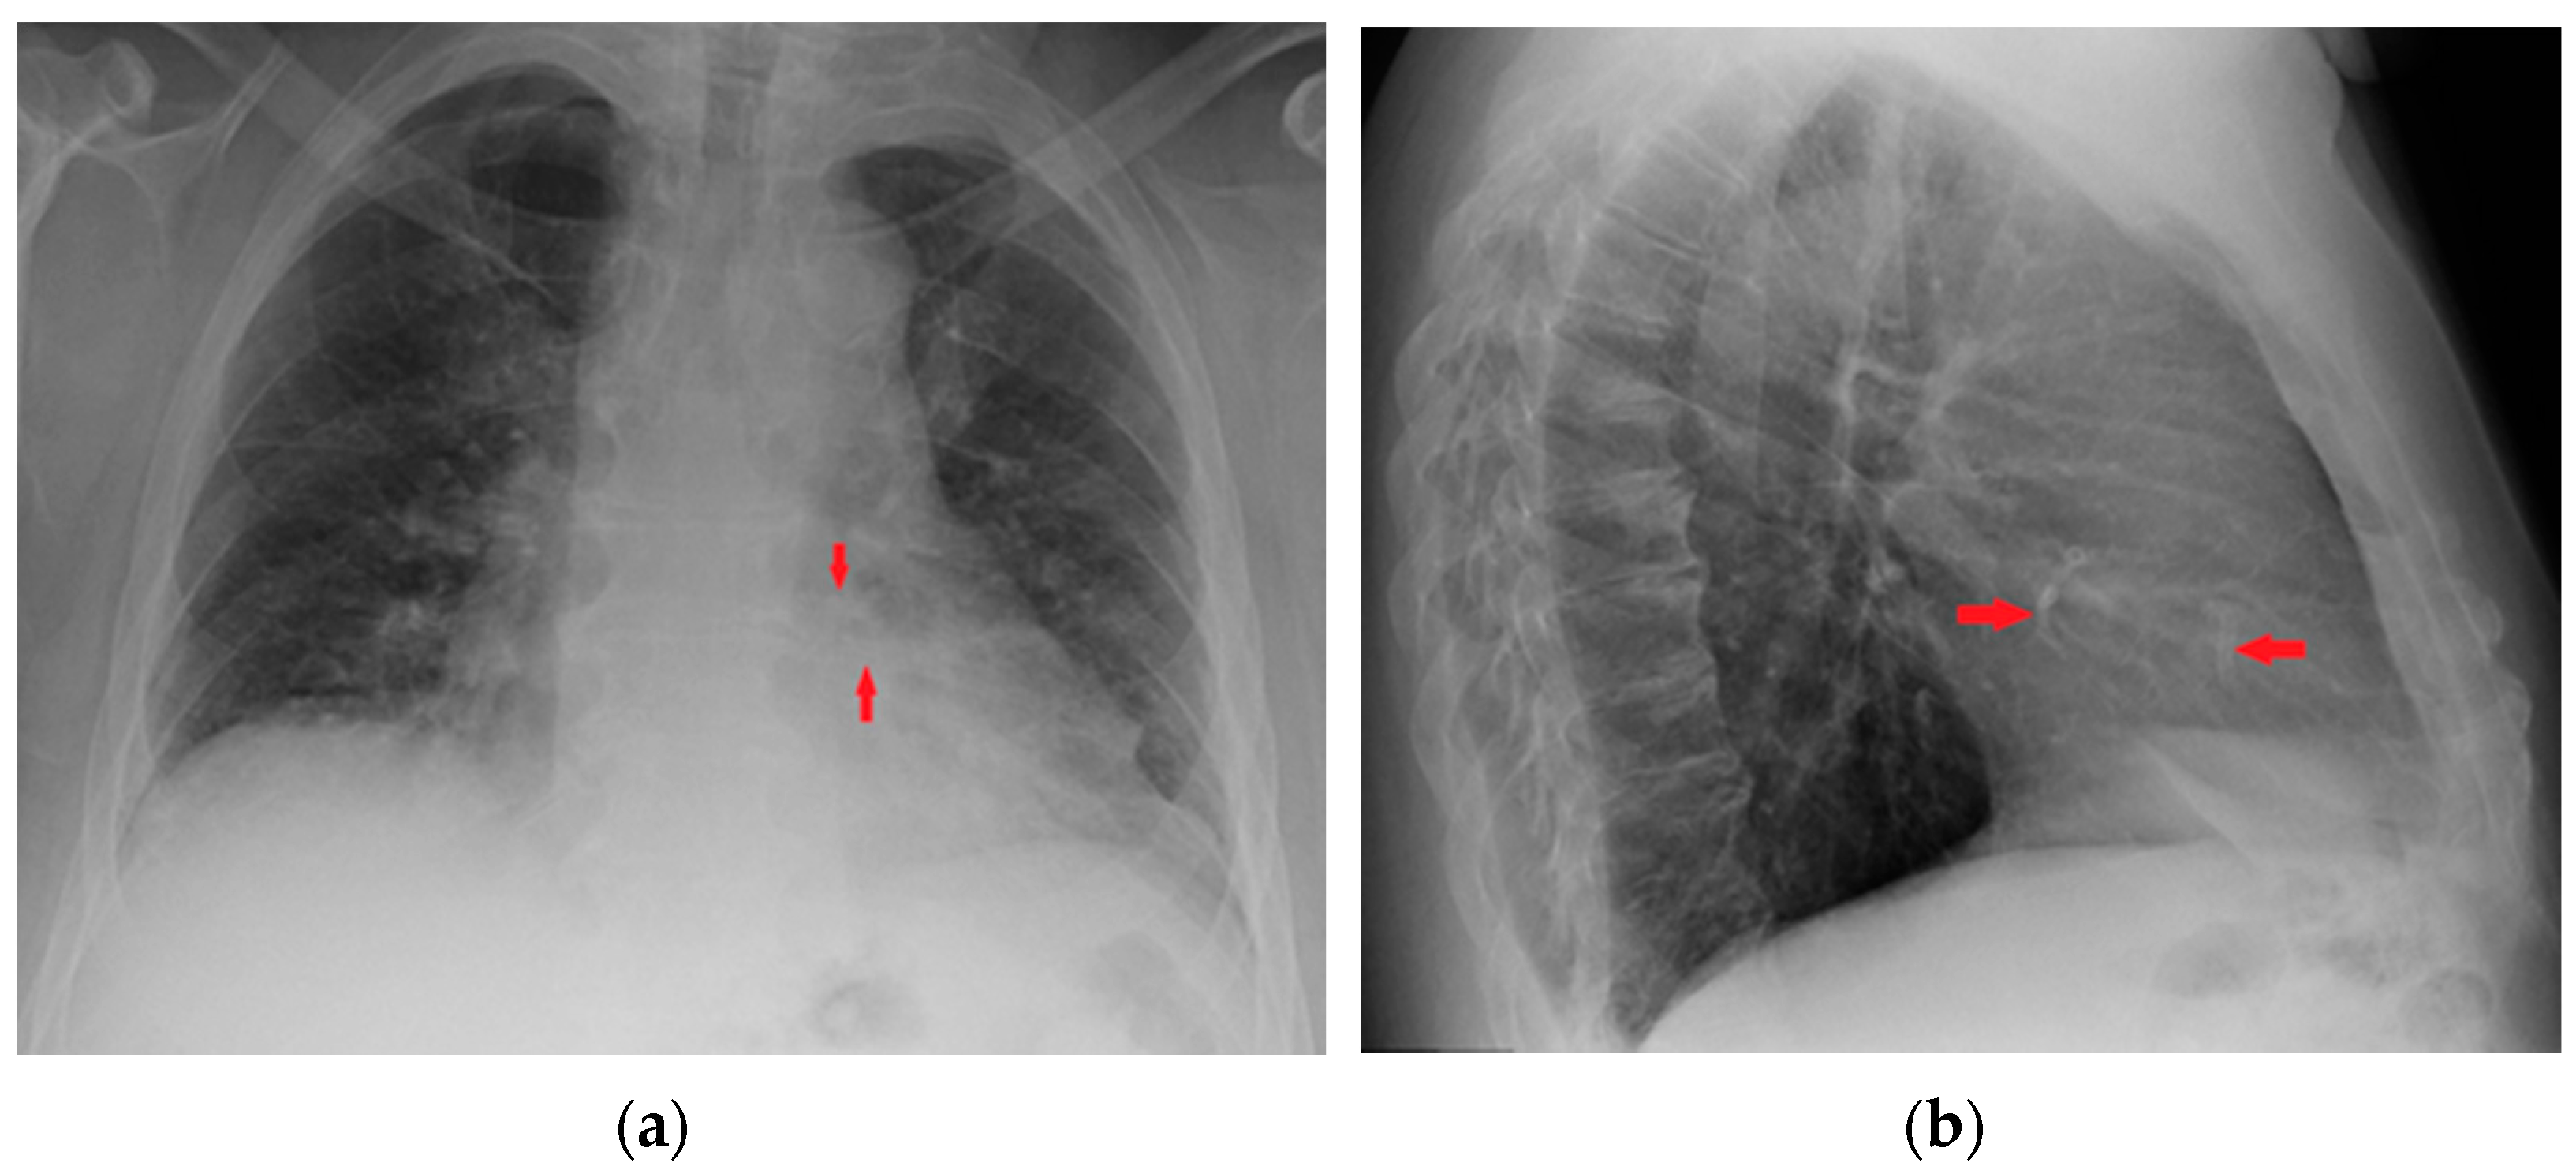

Figure 19.

Coronary artery stents (red arrows), barely visible on the PA projection (a), can be better appreciated on the LL view (b).